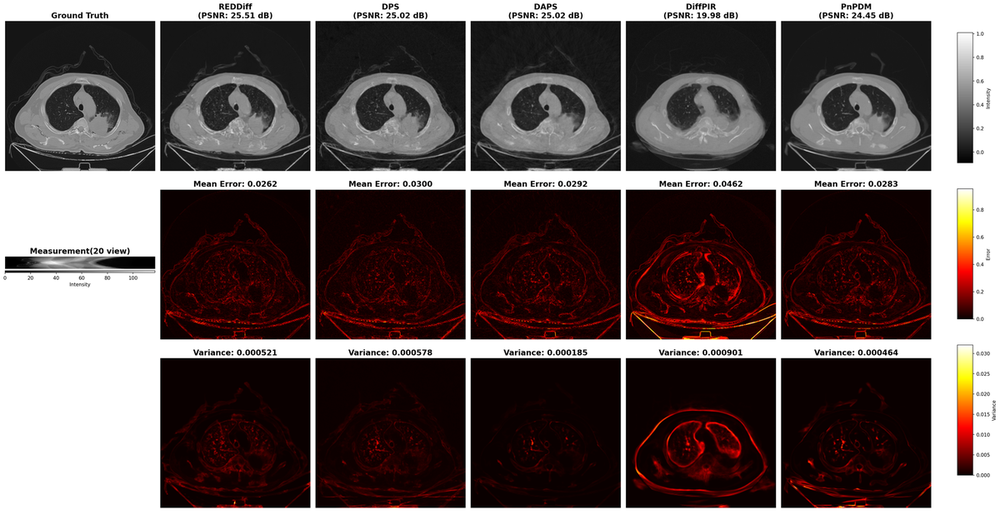

We summarize real-data results using three complementary views: (i) quantitative results with both accuracy and variance metrics across three tasks (Table 2); (ii) qualitative results with reconstructions, error maps and variance maps (e.g., Figs. 7 and  9 ), and (iii) an accuracy–uncertainty summary plot (Fig. 6). In the qualitative figures, the top row shows the highest-PSNR reconstruction among the K=100K=100 samples for each solver (PSNR reported); the middle row shows the corresponding error map with mean absolute error over pixels; and the bottom row reports the pixel-wise variance map aggregated over all KK samples, together with the spatially averaged variance reported.

Figure 7: Sparse-sampling MRI under ×4\times 4 acceleration rate (AR=4).

Several solvers that achieve similar PSNR and visual reconstruction quality, can exhibit substantially different uncertainty behaviors, both in the magnitude and the spatial structure of the estimated variance. For example, DAPS consistently produces a visible background variance across settings in Fig. 7 and 9, and also yields inflated variance along observed directions in Toy Experiment 2 (Fig. 4). Solvers also differ in the stability of their uncertainty behavior across tasks: the MAP solver REDDiff repeatedly shows near-zero variance, consistent with its point-estimation nature, whereas some heuristic solvers are less stable across settings. In particular, DPS shows relatively small variance in Toy Experiment 2 and the CT task, but much larger variance in linear inverse scattering and MRI. This variability is likely driven by sensitivity to algorithmic hyperparameters.

How does uncertainty behavior relate to accuracy performance?

In principle, reconstruction accuracy and uncertainty quantification are not necessarily related. For instance, REDDiff often achieves strong accuracy but produces near-zero variance, which is not a meaningful representation of uncertainty. Moreover, higher accuracy does not imply larger or smaller variance: in the 360-receiver inverse scattering (Fig. 9), DDNM and DDRM differ by roughly 55 dB in PSNR yet exhibit very similar variance levels. These results highlight that accuracy and uncertainty capture two independent aspects of PnPDP solvers, and both must be evaluated explicitly. These phenomenon are consistent with our toy simulation results (Fig. 5), where solvers with similar RMSE have largely different coverage, and some solvers achieve lower RMSE do not recover the observed and null direction variance well.